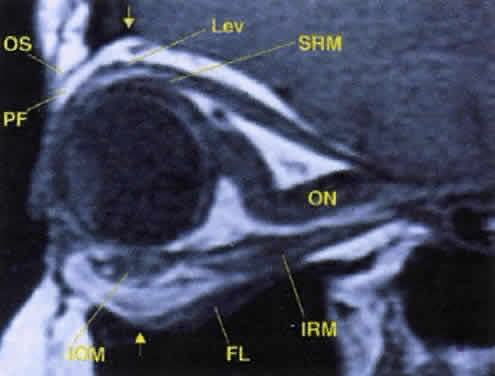

Fig. 17. The optic nerve (ON). A parasagittal MR image demonstrates the 7-mm excess of intraorbital optic nerve, seen as an S shape. Also note the perpendicular relation of the inferior oblique muscle (IOM) to the inferior rectus muscle (IRM). Other findings of anatomic interest in this image include the levator (Lev), the superior rectus muscle (SRM), the orbital septum (OS) arising from the arcus marginalis, and the preaponeurotic fat pad (PF) between the septum and the levator. Note that the orbital floor (FL) is angled upward by 15° to 20° from anterior to posterior.